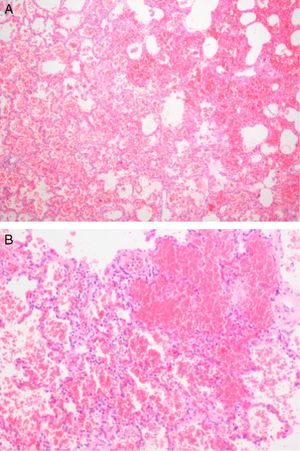

Further investigation showed mild elevation of CK, CK-MB and myoglobin. Reverse transcriptase polymerase chain reaction assay from nasopharyngeal swab samples was positive for H1N1v. The autopsy showed multifocal infiltrates composed mostly of lymphocytes but also some neutrophils, macrophages, plasma cells and eosinophils, associated with myocyte necrosis and ischemia, which was compatible with myocarditis (Figure 2) and excluded the diagnosis of hypertrophic cardiomyopathy. The lung tissue specimen obtained at autopsy showed diffuse pulmonary vascular congestion and extensive alveolar hemorrhage (Figure 1). Additionally, multisystem histological changes including the cardiac and pulmonary alterations described above, and tracheobronchial and intestinal involvement associated with viral infection were evident, leading to a definite postmortem diagnosis of fulminant viral myocarditis.

Small autopsy-based studies have shown complication rates of myocarditis in fatal cases of 39.4% with Asian flu and 48% with Spanish flu.5 All these fatal cases with myocarditis had severe pneumonia and multiple organ involvement, implying that myocarditis was likely to be a terminally ill state of influenza infection,5 as could have been the case with our patient, according to the histopathological findings on autopsy (Figures 1 and 2). By contrast, severe viral pneumonia did not precede myocarditis in the 15 cases reported by Ukimura et al.2 Some patients complained only of high fever, without respiratory symptoms before the onset of myocarditis. The findings imply that the H1N1v may have a high affinity for heart tissue in some susceptible patients. In this patient there was initially thought to be an underlying cardiac disease (hypertrophic cardiomyopathy), which could have increased his susceptibility to cardiac complications, but this comorbidity was excluded by histopathology findings. Despite the presence of tachycardia, hypotension and hypothermia secondary to dehydration at admission, the patient was hemodynamically stable immediately before asystolic cardiac arrest and death.